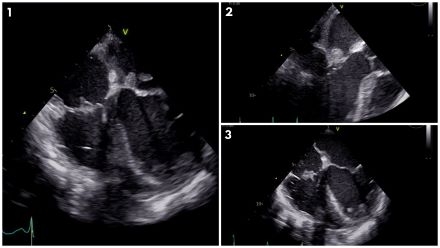

Abstract Body (Do not enter title and authors here): Combined left and right-sided Infective Endocarditis (IE) is rare and typically occurs with underlying predisposing factors such as intravenous drug use, presence of hemodialysis catheters, congenital defects, and intracardiac devices. We present a 62-year-old woman with diabetes, hypertension, and severe peripheral vascular disease, diagnosed with combined left- and right-sided native valve IE despite lack of typical underlying risk factors. She presented with altered mental status and sepsis; blood cultures were positive for Streptococcus group G. Initial transthoracic echocardiogram revealed an 8 mm echogenicity on the atrial aspect of the mitral valve. Subsequently, a transesophageal echocardiogram was performed, revealing a large (2 x 0.9 cm) highly mobile mass on the anterior leaflet of the mitral valve with mild to moderate mitral regurgitation (Figures 1,2); additionally, a small size (0.9 x 0.7 cm) highly mobile mass was seen on the tricuspid valve with mild tricuspid regurgitation (Figures 1,3), meeting criteria for combined left- and right-sided infective endocarditis.